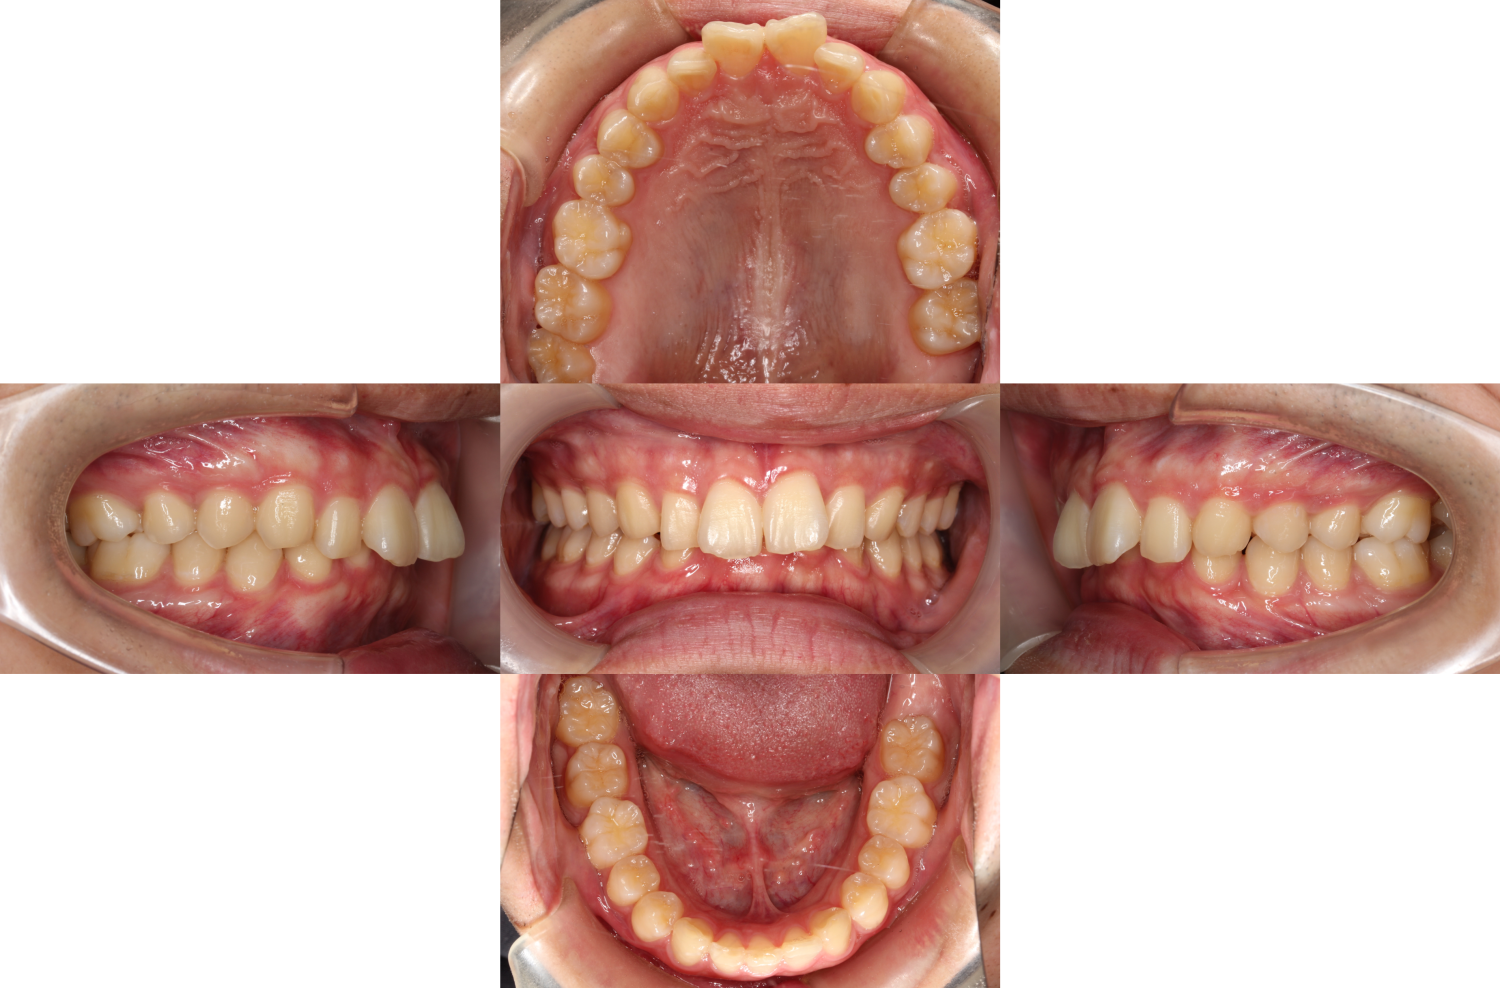

1年1か月後

過蓋咬合・裏側矯正の症例

嚙み合わせが改善し、下の前歯が見えてきました。

バイトアップも必要なくなったため除去しています。